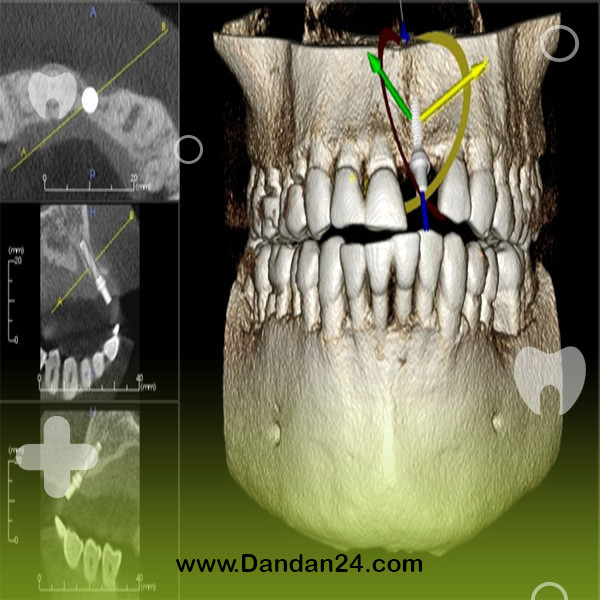

CBCT یا توموگرافی کامپیوتری مخروطی پرتویی، یک روش تصویربرداری پیشرفته است که تصاویری سه بعدی و بسیار دقیق از دندانها، فکها و ساختارهای مرتبط ارائه میدهد. این تصاویر برای دندانپزشکان بسیار ارزشمند هستند، زیرا به آنها امکان میدهد قبل از انجام هرگونه درمان، دید کاملی از وضعیت دهان بیمار داشته باشند.

سیبیسیتی به دلیل دقت بالای تصاویر سهبعدی که ارائه میدهد، به دندانپزشکان کمک میکند تا تشخیص دقیقتری از وضعیت دهان و دندان بیمار داشته باشند. با استفاده از این فناوری، میتوان جراحیها را با تهاجم کمتر و دقیقتر انجام داد که به کاهش زمان درمان و افزایش رضایت بیمار منجر میشود. همچنین، برنامهریزی دقیق درمان با استفاده از سیبیسیتی، امکان ارائه خدمات درمانی با کیفیت بالاتر را فراهم میکند.

عکس CBCT یک روش پیشرفته تصویربرداری در دندانپزشکی است که تصاویری سه بعدی و دقیق از دندانها، فکها و ساختارهای صورت ارائه میدهد. این تکنولوژی به دندانپزشکان کمک میکند تا تشخیصهای دقیقتری انجام دهند و برنامهریزی درمانهای پیچیدهتری مانند ایمپلنت، ارتودنسی و جراحیهای دهان و فک و صورت را به صورت دقیقتری انجام دهند. برای کسب اطلاعات بیشتر درباره CBCT و دنیای دندانپزشکی، میتوانید به سایت جامع دندانپزشکی دندان24مراجعه کنید . این مجموعه در زمینه پیدا کردن کلینیک ها و متخصصین اطرافتان به شما کمک کند . در زیر به چند نمونه از این مراکز اشاره کرده ایم: